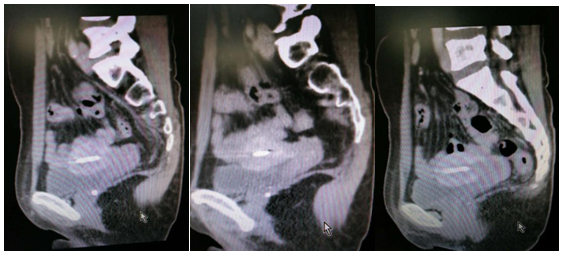

Pelvic CT imaging noted an enlarged thickened heterogenous cervix measuring 4.1 x 3.6 x 3.0cm, with unclear boundaries. Uterus, bilateral adnexa, bladder, rectum appeared normal with no evidence of pelvic lymphadenopathy or pleural effusion. There are many round high density shadows in the pelvic cavity; diameter of the largest of round high-density shadows was 1.0cm. An intrauterine contraceptive ring was seen (Figures 2−5).

Figure 2 Pelvic CT: showing an enlarged thickened heterogenous cervix measuring 4.1 x 3.6 x 3.0cm, with unclear boundaries. Uterus, bilateral adnexa, bladder, rectum appeared normal with no evidence of pelvic lymphadenopathy, pleural effusion. There are many round high density shadows in the pelvic cavity, diameter of the largest of round high density shadows was about 1.0cm. Intrauterine contraceptive ring was seen.